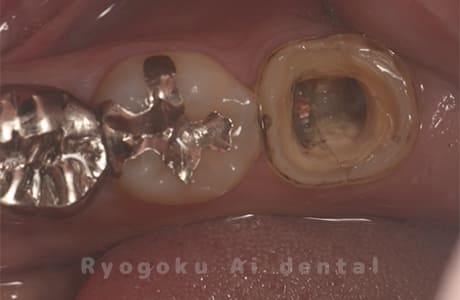

Case13

-

- 原因

- 重度カリエス

- 治療内容

- 自家歯牙移植

- 治療費用

- 220,000円

他院で治療終了を言われたが、物がよくはさまり、噛みにくいとのことでご来院された患者様です。親知らずが残っていたため、自家歯牙移植を提案し、行いました。一年以上経過した現在も経過良好です。

<リスク・副作用>

治療後、痛みや違和感、出血、腫れなどが出る事があります。喫煙者、糖尿病などの方の場合、歯が生着しない場合があります。

Case14

- 右下7番慢性根尖性歯周炎、右下8番智歯周囲炎

右下の腫れが治らないとのことでご来院された患者様です。親知らずの抜歯の必要性もあったため、親知らずの移植を同時に行いました。現在も良好な状態です。